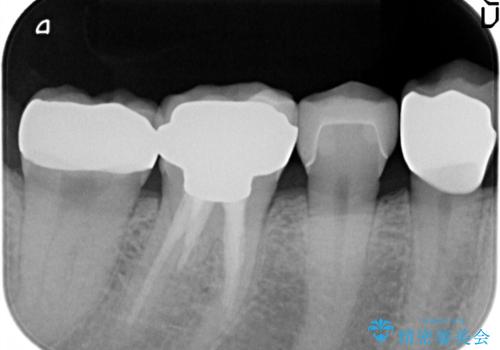

X線検査により、ゴールド修復下に虫歯の再発を多数認めました。

外から見てもわからない虫歯が修復物の下で密かに進行していることがあります。

定期的なX線検査を行うことにより早期発見をすることができます。